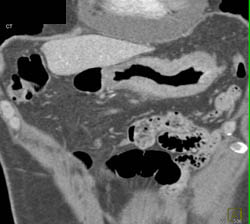

Pill in Stomach Simulates A Mass